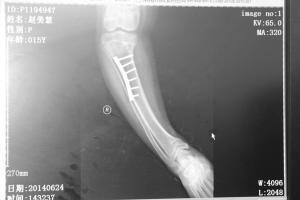

就这样,医生将孩子的左腿和右腿的大腿和小腿两处弯曲最厉害的地方,人为打断,进行重新调整打上钉子固定,让腿变直。整个手术下来,孩子的两条腿一共断了4处。经过医生的重新对位拼接,几个月后,然然O形腿几乎快看不出来了。这让一家人高兴不已。

手术中,医生在然然的左右小腿骨上共打断5处,其中右腿3处,左腿2处。在弯曲最严重的地方,打断骨头,然后将断骨取出三角状骨骼后再接骨让腿骨上下关节在同一轴线上,关节面平行,使得腿骨变直,后将碎骨回填,以防止长短腿的出现。